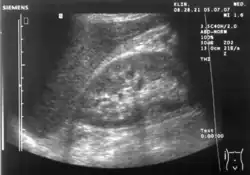

Kidneys: Right and left kidneys measure 11.5 cm and 12 cm in length respectively. No hydronephrosis. Small left lower pole kidney cyst.